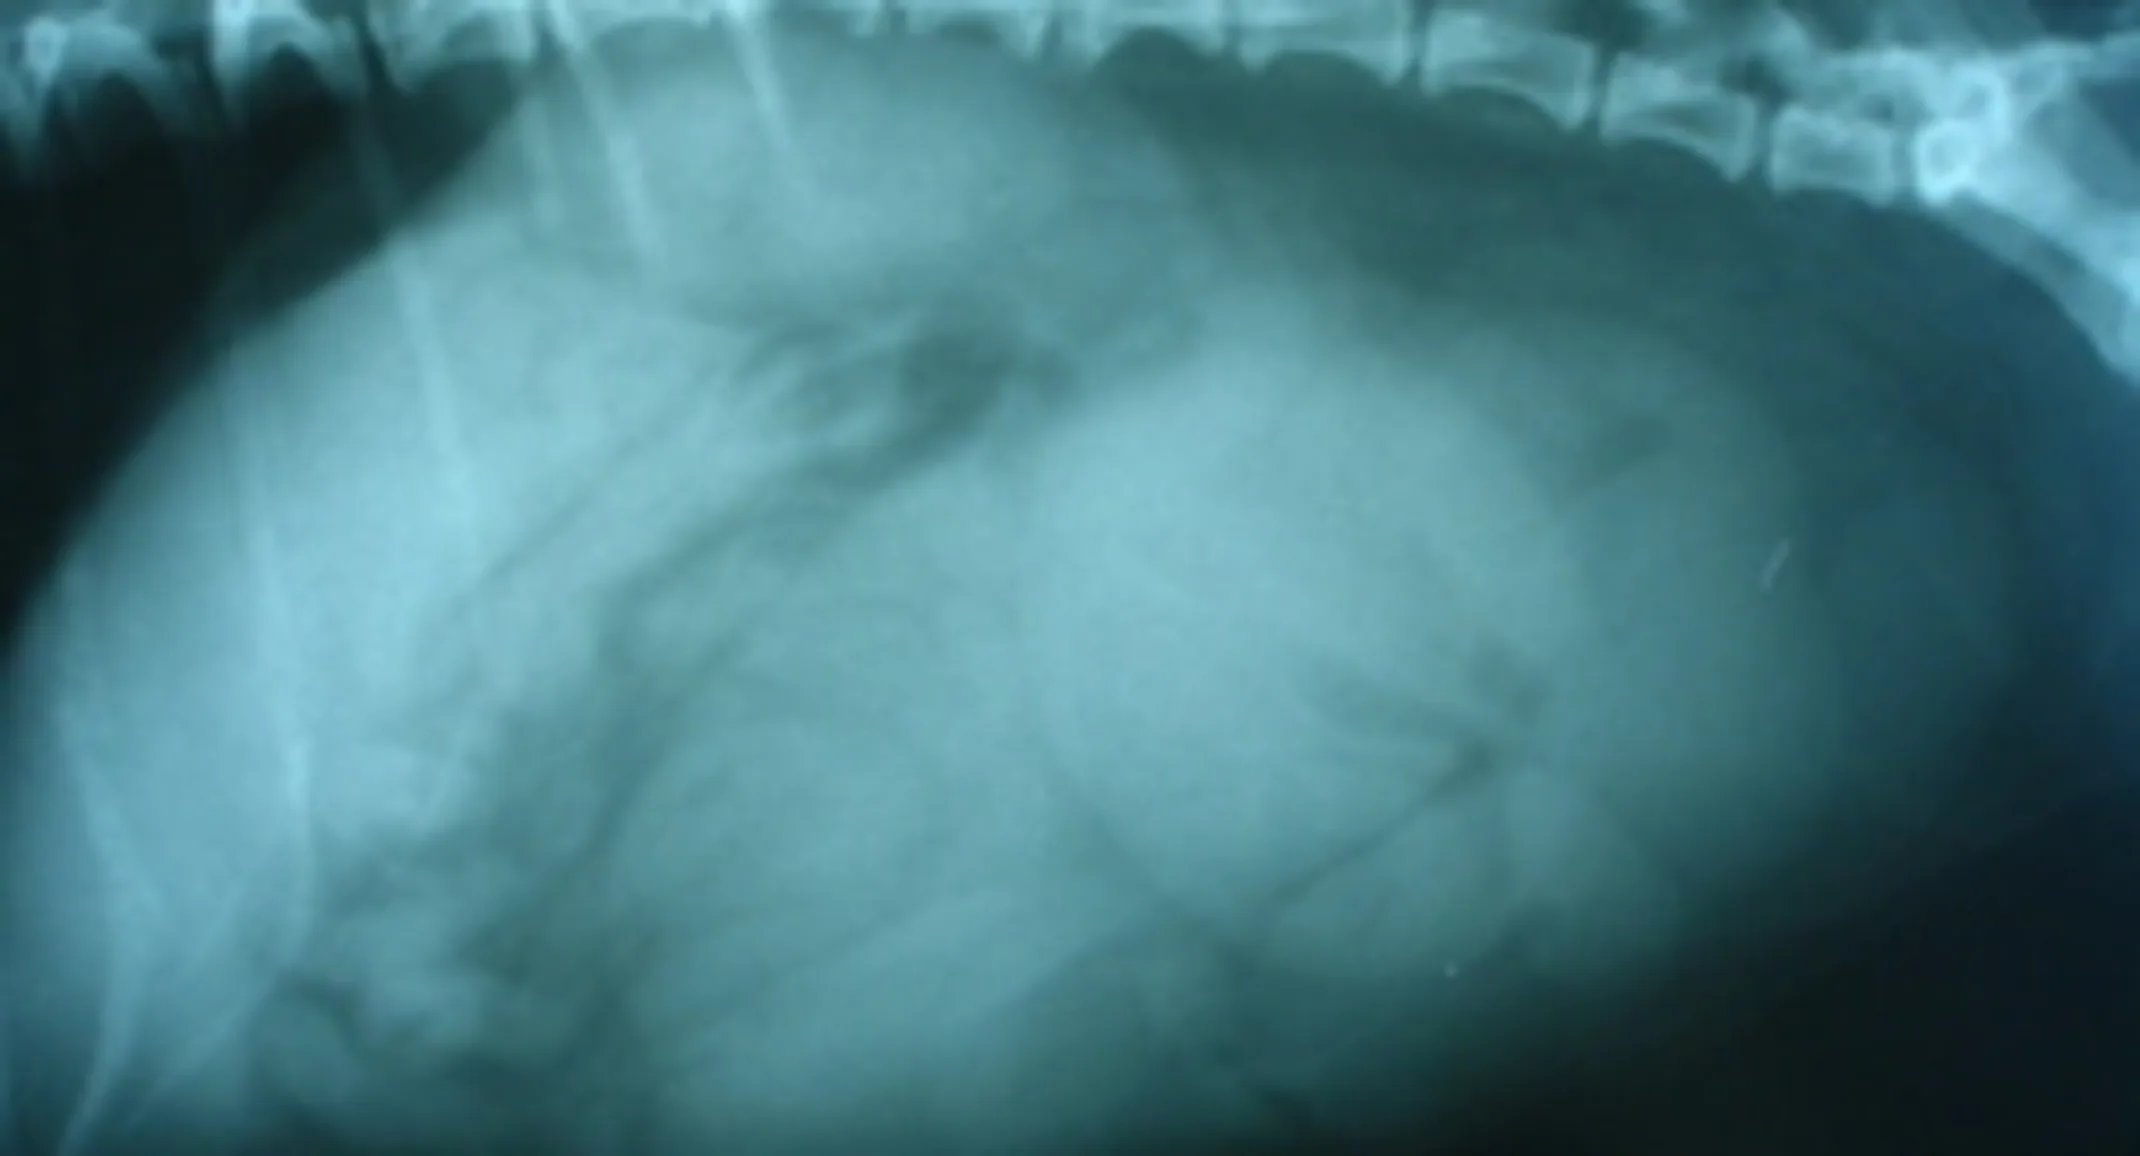

An X-ray (radiograph) and blood work was done which revealed that she had a significant infection going on in her body.

Scimpi’s X-ray (seen on the RIGHT) revealed a large distended whitish structure in the lower back part of her abdomen that was full of fluid (dense structures appear whiter on x-rays while less dense objects appear blacker (i.e. air appears completely black)).

Scimpi had all the signs of a Pyometra, which is a severe infection of her uterus where her uterus fills up with pus and secondarily drained from her vulva. In severe cases, the pus might not drain at all risking the uterus to rupture. If the uterus ruptures, pus will leak into the abdomen which carries a high risk of death.